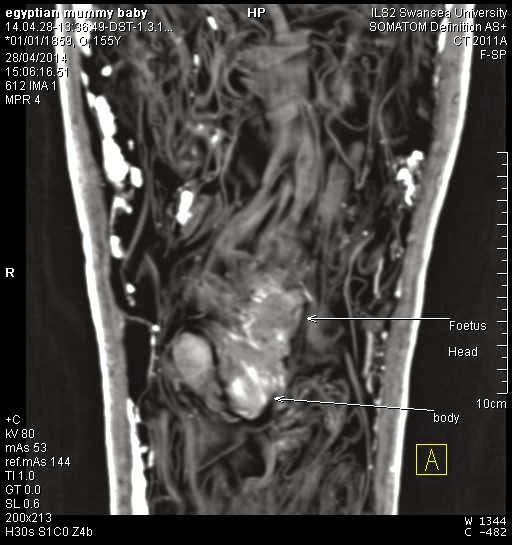

Cercetătorii au observat astfel că în interior, printre diferite bucăţi de material şi amulete, este un fetus mic de doar 10 cm, aflat în poziţie fetală. Avea probabil între 12 şi 16 săptămâni de sarcină când a murit.